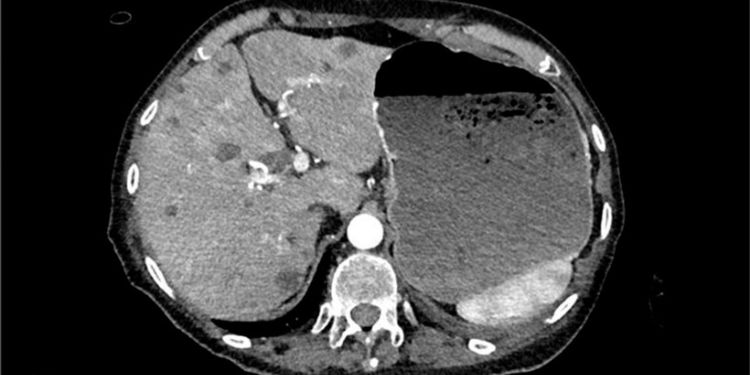

Massive Hematemesis as Initial Presentation of Advanced Pancreatic Adenocarcinoma

DOI: 10.14302/issn.2641-5518.jcci-23-4743

Published on 18 Sep 2023